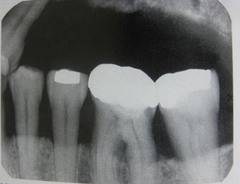

poorly contoured crowns

Front

Back